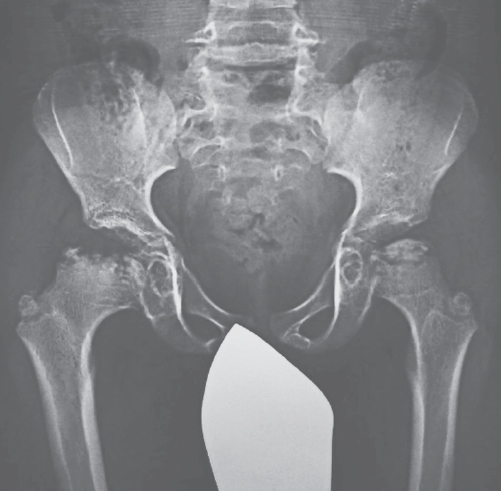

Form B MPS II is more similar to Scheie syndrome. The disease is usually diagnosed at the end of the first or at the second decade of life. Inguinal and umbilical hernias formed early, as well as damage to the cardiovascular system; gargoilism-like facial changes occur, as well as signs of dysostosis multiplex (Fig. 4), joint stiffness (Fig. 5), sensorineural hearing loss, retinopathy, possible obstruction of the airways, sleep apnea, and carpal tunnel syndrome [9]. The course of the disease is slowly progressive. Life expectancy varies widely. One of the typical complications in older patients is narrowing of the tracheal lumen, leading to the need for stenting and/or tracheostomy. The respiratory or heart failure is the most common cause of early death of patients in the second or third decade of life.

Fig. 5. Hip changes in MPS II patients

Рис. 5. Диспластические и дистрофические изменения тазобедренных суставов при